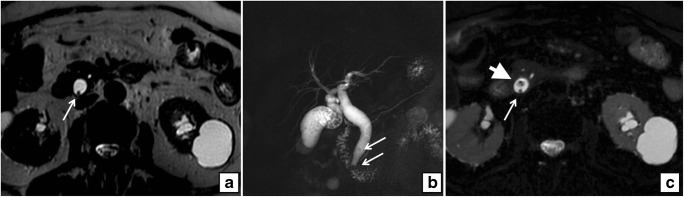

On preoperative US examination, 5 out of 104 patients demonstrated a dilated CBD and, among them, only one patient (20%) presented CBD lithiasis on MRCP, whereas 6 out of 99 patients (6%) with normal choledocal diameter showed CBD lithiasis (Figs. 1, 2, 3, and 4).